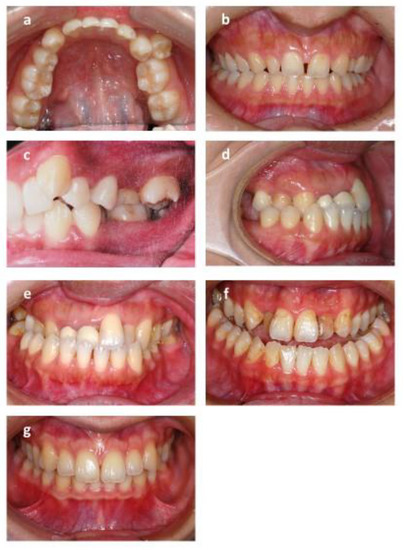

The skeletal relationship between the maxilla and mandible of orthodontic patients was categorized as Class I, Class II, or Class III [35,36,37,38] (Figure 1 and Figure 2). Steiner’s analysis [39] and Tweed analysis [40] were used for the measurements according to the analysis of St. Louis University in the United States, where the first author was trained for her orthodontic graduate program. The dental relationship between the maxilla and mandible of orthodontic patients was defined as molar Class I, Class II, or Class III (Figure 3). The DMFS index was expressed as the total number of teeth that were decayed (D), missing (M), or filled (F) in an individual with permanent dentition. There were five surfaces (facial, lingual, mesial, distal, and occlusal) for the posterior teeth and four surfaces (facial, lingual, mesial, and distal) for the anterior teeth when the DMFS index was calculated.

Figure 1. The reference lateral cephalometric radiographic tracing points used in the study. A point: The innermost point on the curvature of the surface of the maxillary bone. B point: The innermost point on the contour of the mandible. Go: gonion: the intersection of the line tangent to the posterior and inferior angle of the mandible. Me: menton, the most inferior point on the mandibular symphysis. N: nasion, the most anterior point of the intersection between the nasal and frontal bones (frontonasal suture). S: sella, the midpoint of the sella turcica. Po: porion, the most superior point of the contour of the external auditory meatus. Or: orbitale, the most inferior point on the margin of the orbit.